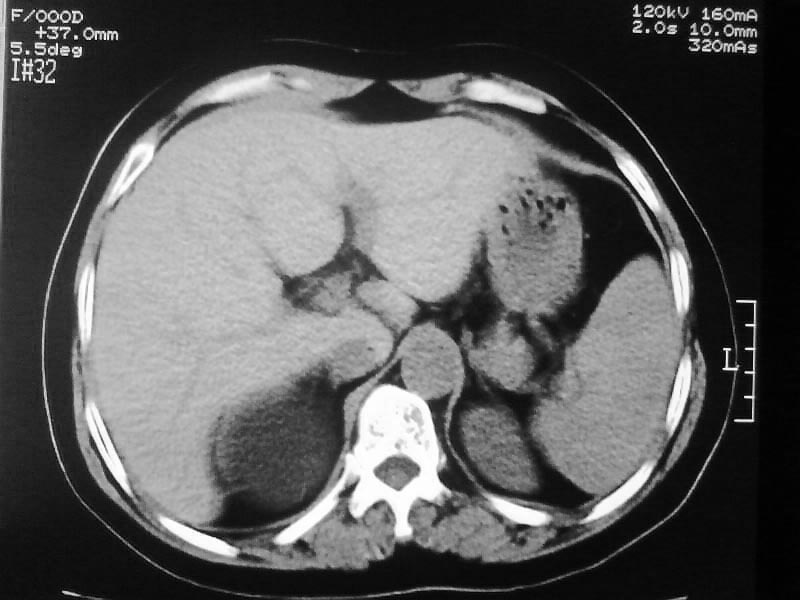

标题: CT20044:女,45岁,腰痛2年,双肾结石,右输尿管结石,右肾重度积 [打印本页]

标题: CT20044:女,45岁,腰痛2年,双肾结石,右输尿管结石,右肾重度积

其内见多房性分隔考虑多囊肾

加扫下输尿管和膀胱吧,先排除下面的大结石所致的积水;

不像普通的积水,密度像是积脓;

多囊肾可以排除。

支持双肾结石、右输尿管上端结石,右肾重度积水